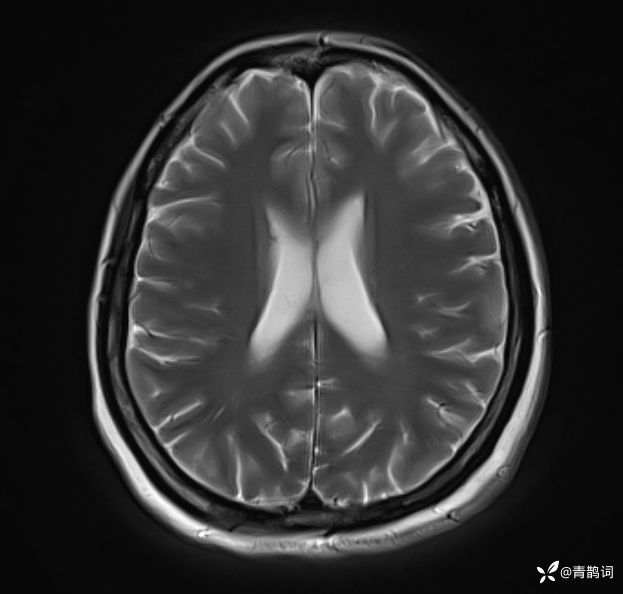

病例分享 | 45岁女患,7年的病史,结合影像学,如何诊断?

1、患者:女, 年龄:45岁

2、主诉:走路不稳渐加重7年,饮水呛咳伴头晕2年渐加重。

3、简要病史:患者于入院前7年出现走路不稳,表现为行走右偏,逐渐加重,易跌倒、不能自理;近2年出现饮水呛咳、吞咽困难及头晕;病程伴有耳鸣、反应迟钝,无恶心、呕吐。既往否认高血压、否认糖尿病、否认冠心病。

4、体格检查:体温36.0℃,脉搏80次/分,呼吸20次/分,血压140/70mmHg。查体:神清,构音障碍;眼球运动自如,双水平性眼震,左视时明显;双侧瞳孔等大同圆,左:右=3mm:3mm,对光反射灵敏;双侧额纹对称,双侧鼻唇沟对称;伸舌居中;四肢肌力4级,肌张力减低,四肢腱反射亢进,双侧Babinski征阳性;粗测感觉未见明显异常;四肢共济运动完成差,左侧为著;脑膜刺激征阴性。

入院后完善磁共振:

T2: